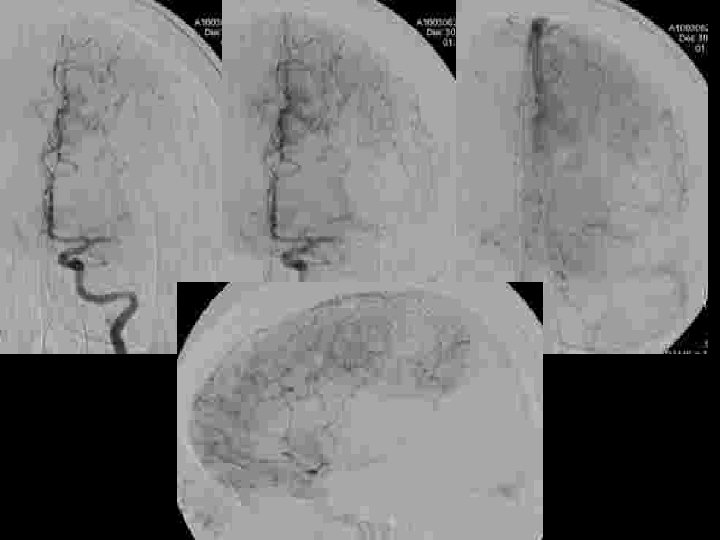

OCCLUSION du « T » CAROTIDIEN : RESULTATS DE LA THROMBOLYSE INTRA-ARTERIELLE CHEZ 21 PATIENTS • Etude rétrospective de 21 patients traités dans les 6 heures – – – 14 femmes, 7 hommes Age: 58. 4 ans (31 -84) NIHSS à l’admission: 18. 9 (12 -33) Délai de traitement: 262. 4 minutes (180 – 330) maladie cardio-embolique : 10 patients (47, 7%)

OCCLUSION du « T » CAROTIDIEN : RESULTATS DE LA THROMBOLYSE INTRA-ARTERIELLE CHEZ 21 PATIENTS • circulation collatérale – Artère communicante antérieure • Présente • Absente 14 7 – Opacification rétrograde de l’ACM • Jusqu’à la région insulaire • Incompléte • Absence 3 cas 9 cas • Technique • thrombolyse Mécanique • Mécanique +chimique 6 cas 15 cas * Urokinase (900. 000 UI): 7 cases * Actilyse (0, 9 mg/kg): 8 cases + 1/15 stenting carotidien cervical (sténose >90%)

Thrombectomie mécanique « Catch , Balt» + 70 mg r. Tpa

Résultats Recanalisation • Immediate en Angiographie : – TIMI 0 6/21 – TIMI 1 5/21 – TIMI 2 -3 10/21 • DTC à 24 heures: Recanalisation - 13 cas (62%) Hémorragies 9 cas Transformation hémorragique 2/9 Hématome symptomatique 7/9 à 3 mois m. RS 1 m. RS 3 -4 décès 2/2 1/7 3/7

EVOLUTION CLINIQUE • A J 7 – – • A 3 mois (Modified Rankin Scale –m. RS) – – – • 7 morts (33, 3 %) (3 complications hémorragique) 14 patients survivants avec un score NIH de 6. 8 m. RS 0 -1 m. RS 2 m. RS 3 -4 10 patients 1 patient 3 patients résultats m. RS 0 -1 m. RS 2 m. RS 3 -4 m. RS 6 47. 7 % 14. 2 % 33. 3 % 4. 8 %

Recanalisation / Evolution Clinique

Conclusions • Le pronostic des occlusions en T de la carotide interne reste sévère – recanalisation (TIMI 2 and 3) moins fréquente que pour M 1 – complications hémorragiques plus fréquentes (7/21) • La thrombolyse intra artérielle améliore le pronostic • La thrombectomie mécanque améliore le taux de recanalisation et son délai